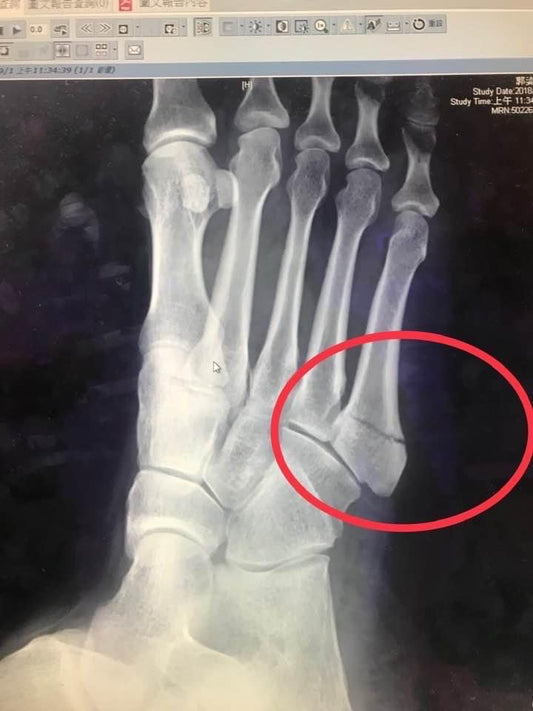

骨折快速癒合的真實案例:山金車及酸痛按摩油